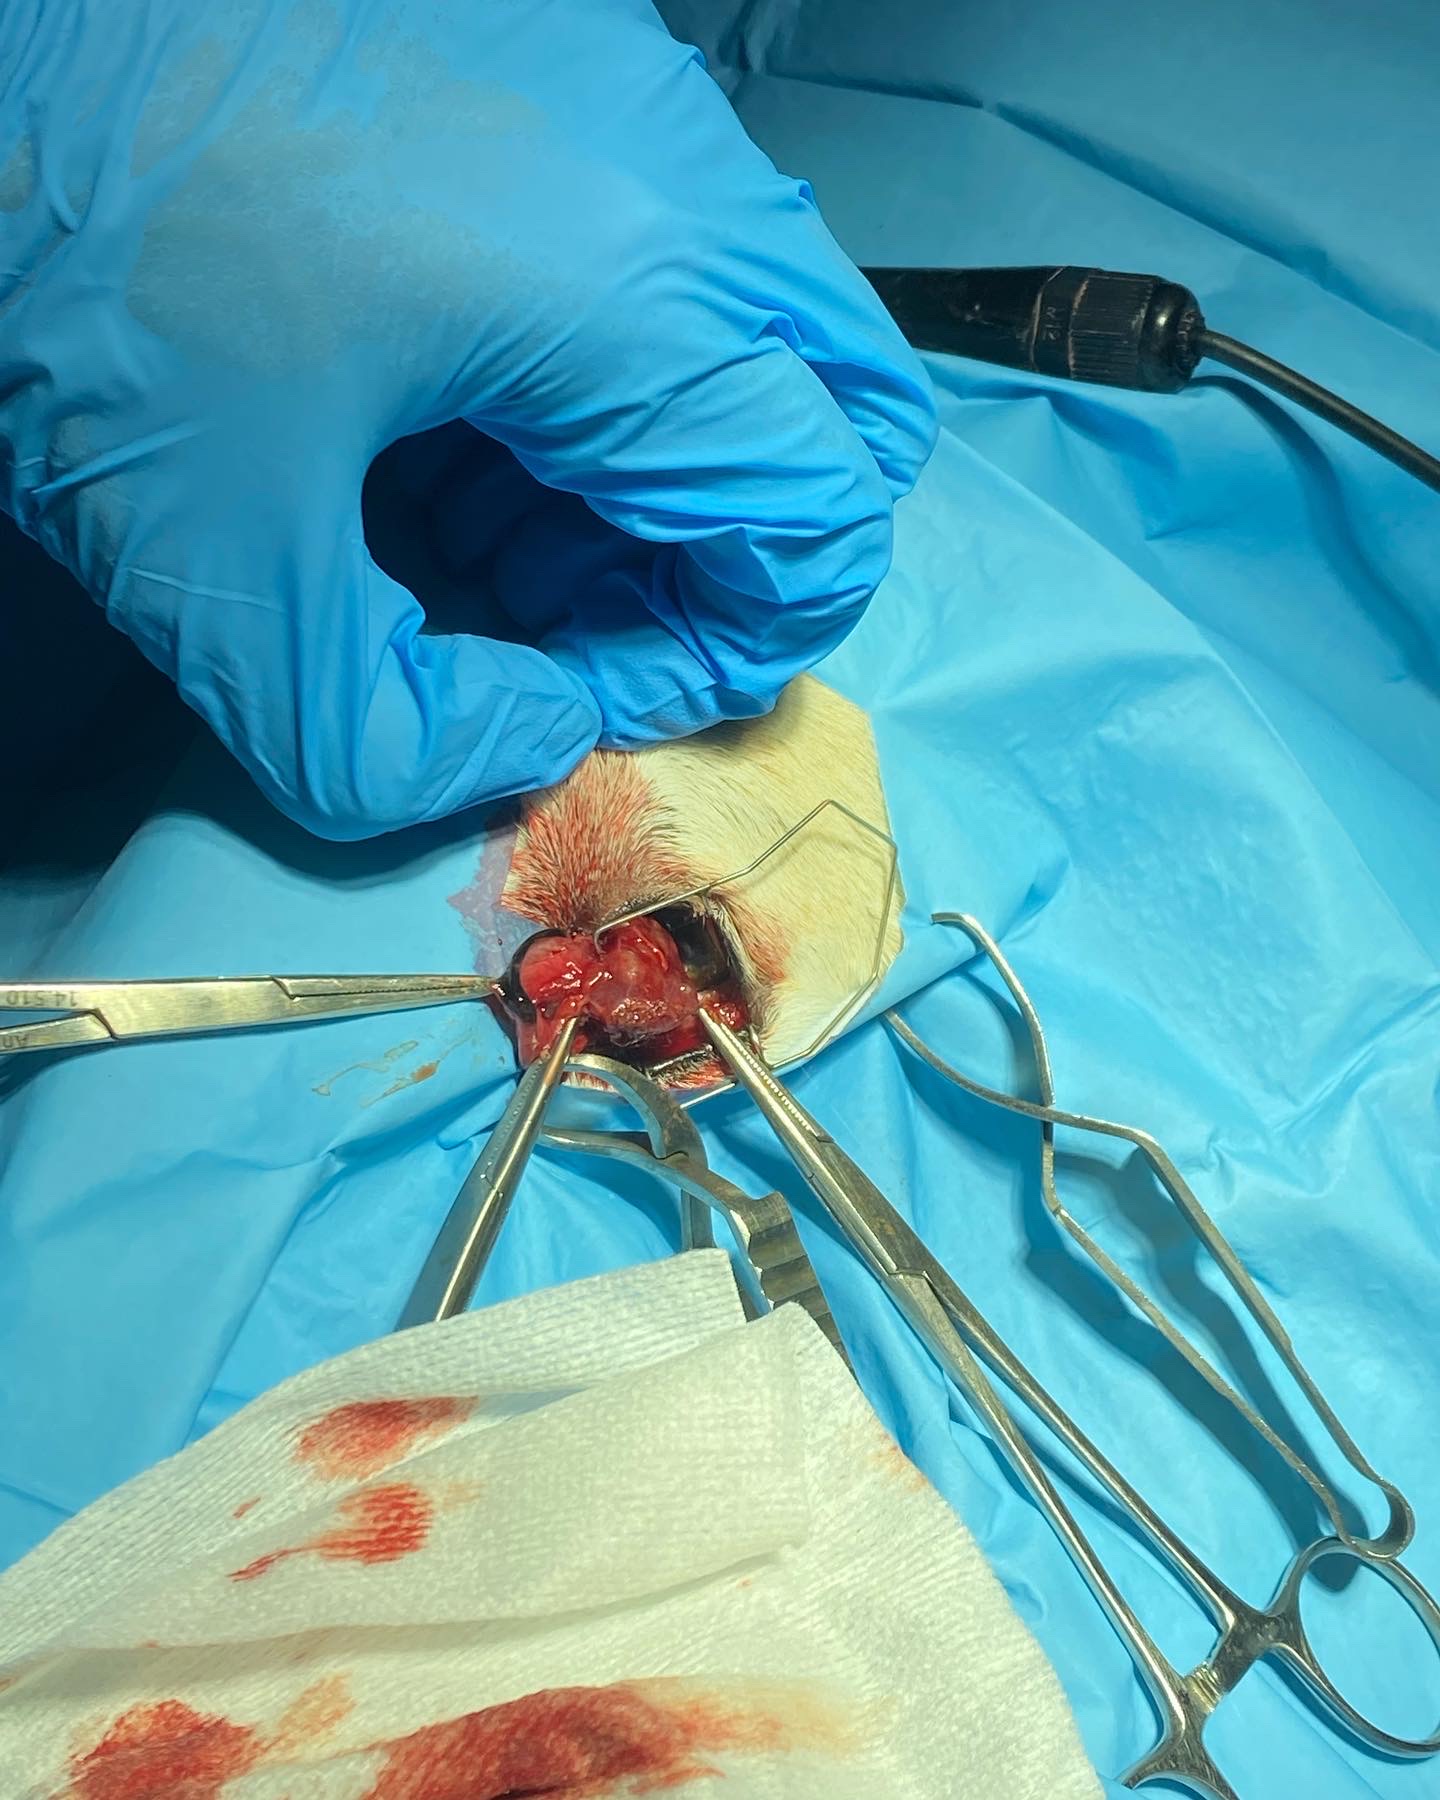

- Cirugía de Tejidos Blandos